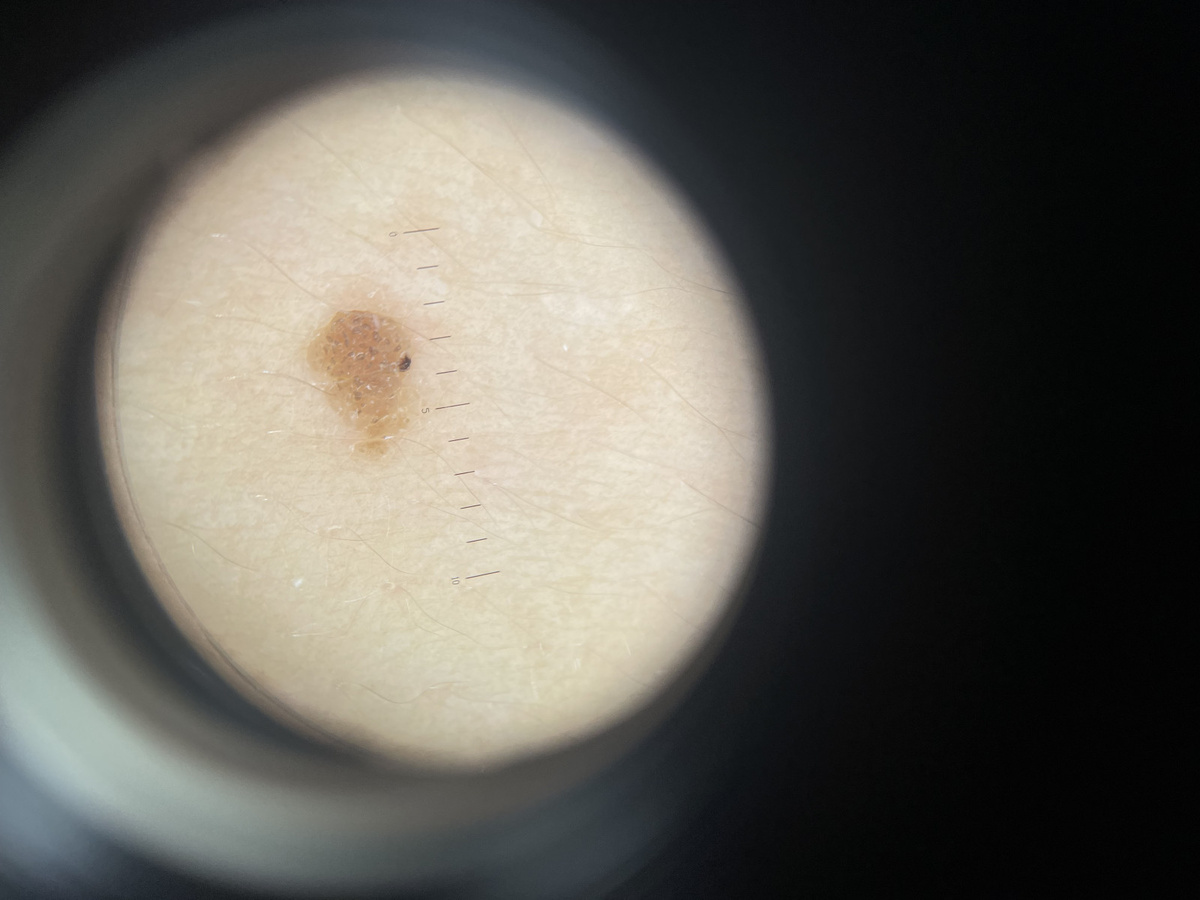

Пять главных признаков «перезагрузки» родинки (Система ABCDE)

Специалисты используют международный протокол для оценки риска. Если ваша родинка изменила форму, проверьте её по этим пунктам:

• А — Асимметрия (Asymmetry): Если вы мысленно проведете линию через центр родинки, две её половины должны быть зеркальны. Если одна сторона стала «расти» в бок или менять очертания активнее другой — это сигнал.

• В — Границы (Borders): У здоровой родинки края четкие и ровные. Если границы стали размытыми, «рваными», зазубренными или напоминают географическую карту — это повод для визита к врачу.

• С — Цвет (Color): Тревогу вызывает не просто темный цвет, а неравномерность. Если в родинке появились вкрапления черного, серого, голубого, красного или белого цветов — это признак того, что клетки ведут себя хаотично.

• D — Диаметр (Diameter): Родинки крупнее 6 мм (размер ластика на карандаше) требуют пристального внимания, хотя меланома может быть и меньше.

• E — Эволюция (Evolution): Это самый важный пункт после 50. Любое изменение (рост, зуд, появление корочек, кровоточивость, изменение высоты) — это главный маркер опасности.

Просто осмотра глазами в 2026 году недостаточно. Современный протокол включает:

• Цифровая дерматоскопия: Врач изучает родинку под увеличением в 20–100 раз с использованием специального света. Это позволяет увидеть структуру глубоких слоев кожи.